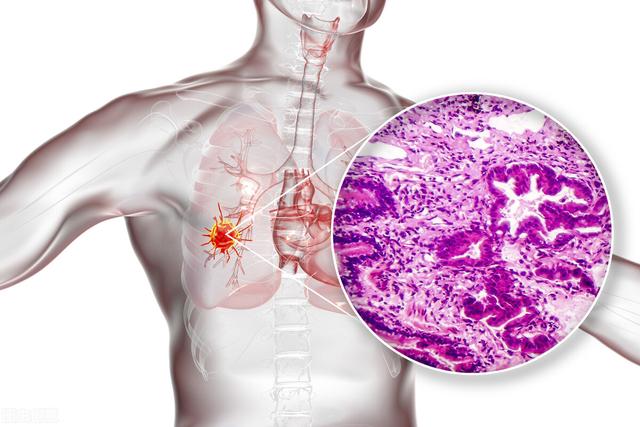

肺がんは腺がん、扁平上皮がん、大細胞がん、小細胞がん、カルチノイドがんなどに分類される。これらの癌が小さい場合は、大きい場合ほど典型的な癌ではない。

これは外科的に確認された肺腺癌の症例である。

肺の小さな悪性結節はしばしば典型的な悪性腫瘍の徴候を示し、結節内部の密度はしばしば不均一で、初期の結節ではすりガラス状になったり、すりガラス状の密度が混在するものもあり、結節の一部に小さな空洞が見られることもある。悪性結節は栄養補給のために大量の血液を必要とするため、辺縁部にはしばしば短いバリが浸潤しているのが見られ、血管集塊と呼ばれる小さな血管の集合体が小結節の小血管に近接して見られることもあるため、辺縁部はさらに典型的である。